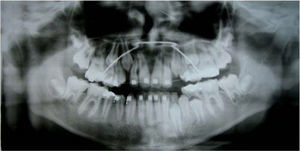

Análisis radiológicoEn las radiografías panorámicas y periapicales las estructuras esqueletales y alveolares son normales a excepción de los ápices de los incisivos centrales y lateral superior derecho que no están bien delimitados.

Un cefalograma fue hecho en oclusión céntrica así como los análisis cefalométricos de Steiner, Jarabak y Ricketts (Cuadro I).

RESULTADOS DEL TRATAMIENTOLa mordida cruzada anterior del paciente fue eliminada y las radiografías y trazos cefalométricos de Steiner, Jarabak y Ricketts fueron repetidos al término de la fase ortopédica.